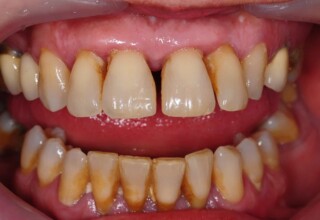

Extensive case with crowns in almost all teeth

Extensive case with crowns in almost all teeth due to extensive wear, old restorations, posterior root canals and aesthetic concerns. Patient (60years old) presented with intense bruxism which he never had treated. Consequently, he obtained very deep cervical abrasions which jeopardized tooth integrity. Restorations (fillings) were executed mainly with adhesive resinous materials and three custom cast post and cores. Temporary crowns were placed to evaluate the desired size, shape and position of the teeth before permanent crown fabrication.